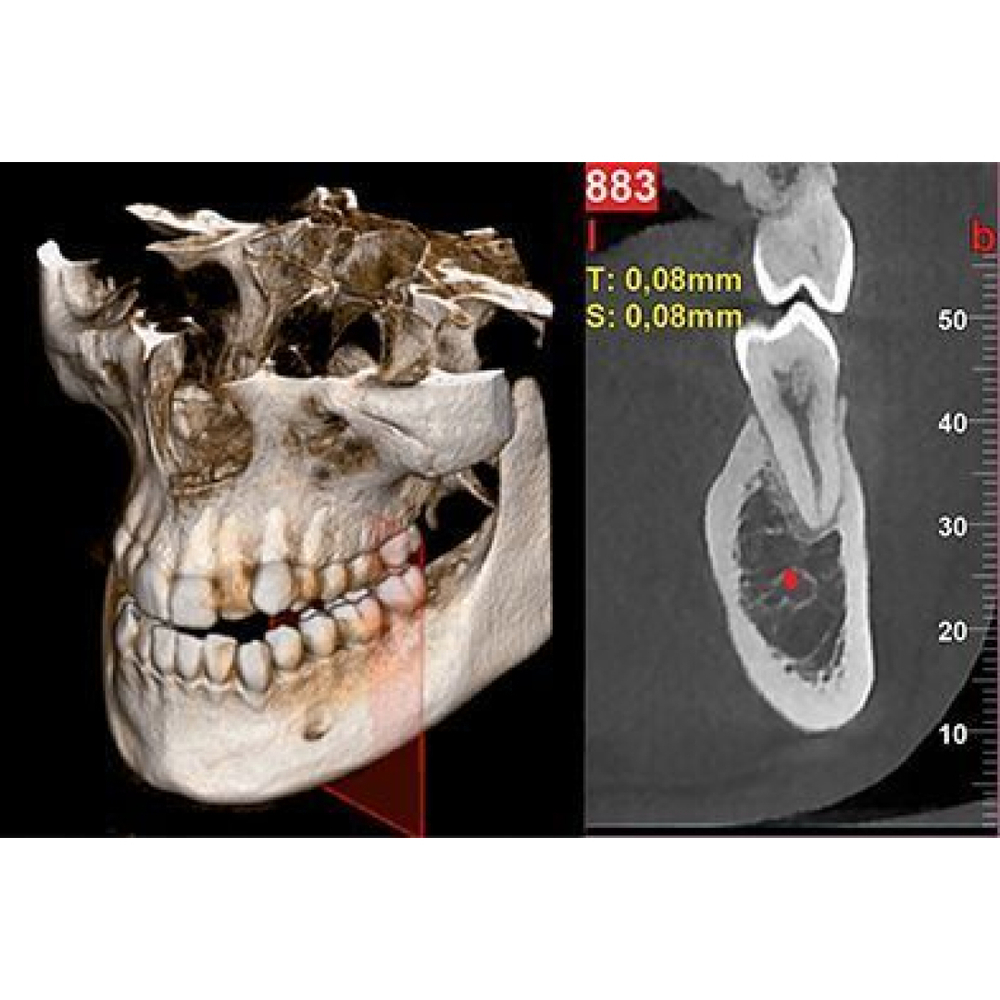

Программное обеспечение NewTom NNT предлагает все функции, необходимые для выполнения, обработки, вывода на экран и передачи 2D и 3D результатов обследования. NNT также предоставляет различные режимы и функции приложения, специально предназначенные, чтобы планировать лучшее лечение в области имплантологии, эндодонтии, пародонтологии и рентгенографии, а также в челюстно-лицевой хирургии.

Совершенство в 3D

NewTom GO генерирует выдающиеся объемные изображения и для каждого FOV в диапазоне от 6х6 до 10х10 см. Выбор из 3 протоколов позволяет адаптировать требуемую дозу рентгеновского излучения к конкретным потребностям: от очень низкой для быстрого сканирования, необходимого при последующих хирургических проверках, до регулярной для планирования лечения, до очень высокого уровня детализации для анализа микроструктур.